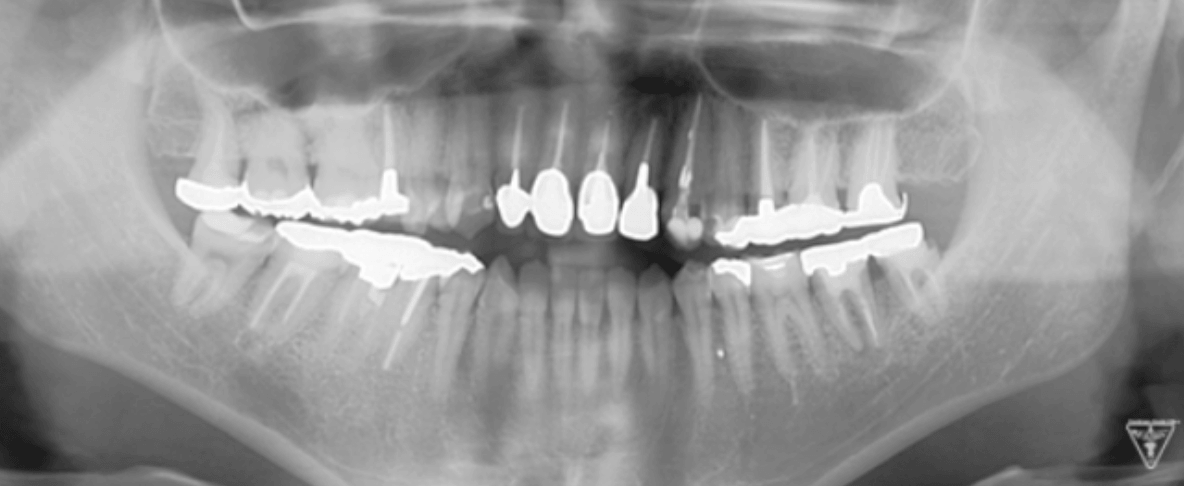

治療前